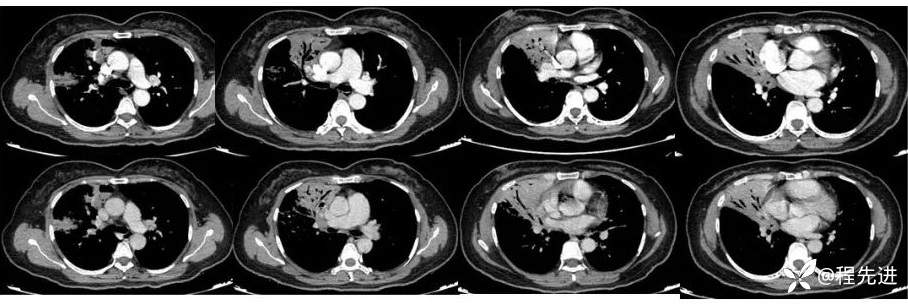

直接CT增强: